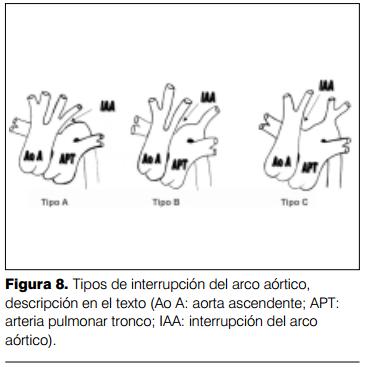

La interrupción del arco aórtico se presenta en el 1% de todos los recién nacidos con cardiopatía congénita, pero es responsable del 4% de las muertes cardíacas en menores de un mes de edad (11,12). Su existencia se debe a la obliteración del cuarto arco aórtico izquierdo. Puede estar ubicada distal al origen de la arteria subclavia izquierda (tipo A), o entre la arteria carótida primitiva izquierda y la arteria subclavia izquierda (tipo B) o entre el tronco arterial braquiocefálico y la arteria carótida primitiva izquierda (tipo C) (13) (figura 8). El flujo sanguíneo para el territorio distal a la interrupción depende de la existencia de un ductus arterioso permeable, constituyendo así una circulación ductus dependiente. El cierre espontáneo del ductus arterioso determina una hipoperfusión de todo el territorio dependiente de la aorta descendente, sobre todo el renal, con la aparición de acidosis metabólica y estado de shock cardiogénico, que se revierte con la infusión de prostaglandina E1 (14). Suele asociarse con frecuencia una comunicación interventricular sobre todo en los tipos B y C. La saturación arterial de oxígeno en el sector proximal a la interrupción es normal y en el sector distal está descendida (15).